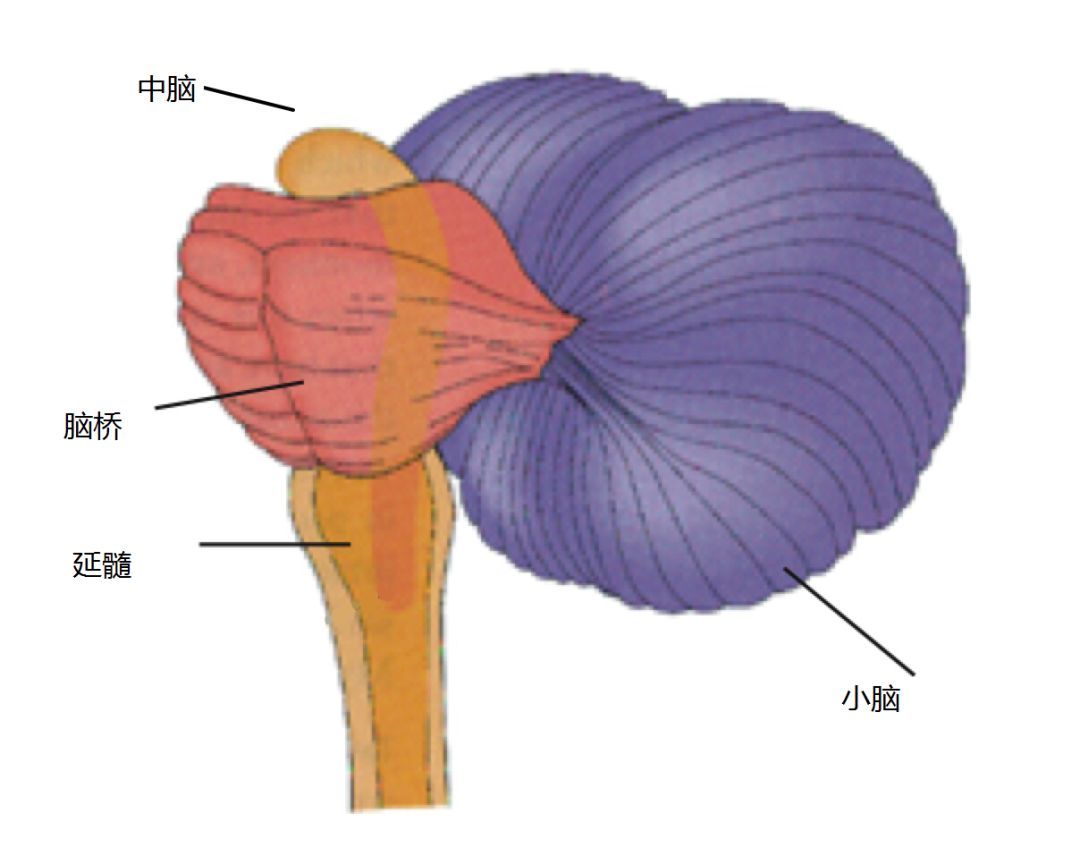

爬虫类脑:脑干和小脑

这是我们大脑里最古老的一部分

就是图中青蛙大佬所占据的那部分。事实上,一个真的青蛙的脑和人类脑的这一部分是非常相似的,下图是青蛙脑的照片。

延髓基本上做着那些让你不要死的工作。它控制那些无人赏识但是至关重要的无意识行为,好像心脏的跳动、呼吸、血压,以及当它觉得你中毒的时候让你呕吐。

脑桥则是这也做点,那也做点的百搭。脑桥控制吞咽、膀胱、脸部表情、拒绝、唾液、泪水和体态。

中脑则比脑桥更杂。中脑的地位其实很尴尬,它的每一个功能都和大脑另外某个部位的功能重复。中脑涉及视觉、听觉、运动控制、警觉、体温控制,以及其它若干个由脑的其它部位已经在做的事情。大脑对于中脑也不是很买账,整个大脑可以分为前脑、中脑和后脑,前脑和后脑都由多部分组成,范围很大,唯有中脑是孤立的一小块。

脑桥和中脑有一个值得单独提出的功能是它控制眼球的自主移动,所以如果你现在在转动你的眼球的话,其实就是脑桥和中脑帮你达成的。

小脑保证你能够平衡、协调和正常的移动。